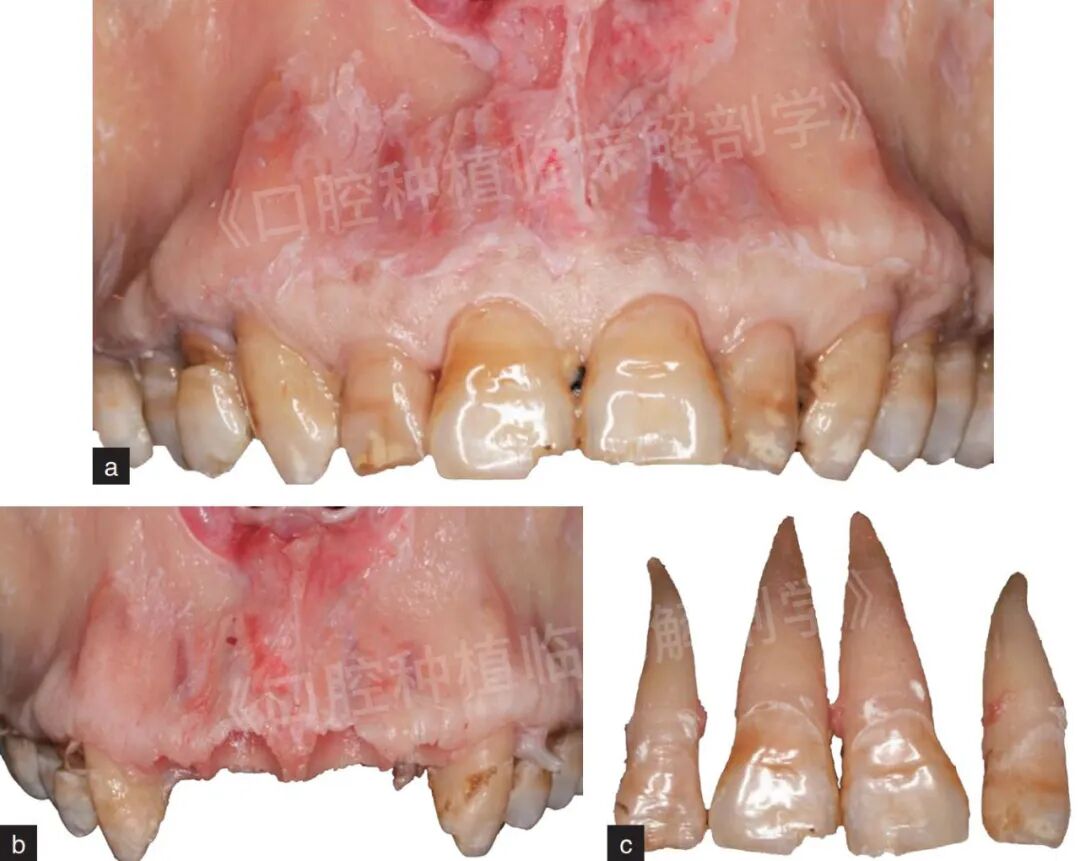

图10 选择下颌牙列完整冰鲜头颅模型,微创拔除下颌前牙。a为完整的下颌牙列;b为微创拔除下颌前牙;c为拔除的牙齿冠根完整